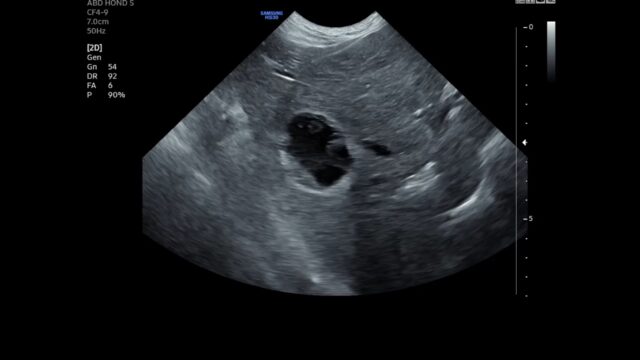

Hond met sludge in de galblaas en steen in de urineblaas

Ik heb een vraag over een 10-jaar oude vrouwelijke Keeshond. Ze werd aangeboden met hematurie en strangurie. Geen andere klachten. UOZ: SG 1048, pH 6.5, WBC en RBC, geen kristallen, GLU (50mg/dL), KET 15.0 mg/dL, BIL 1.0 MG/dL. Omwille van de veranderingen in het UOZ ook een BOZ uitgevoerd: ALT: 299 U/I (10-125), ALKP 1676 (23-212), GGT…